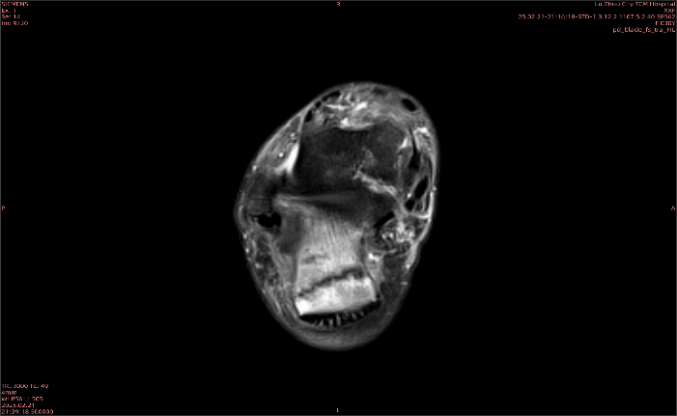

隱性骨折在MRI表現(xiàn)為T1WI序列上見由關(guān)節(jié)面向骨干走行的形態(tài)各異低信號(hào)區(qū),有線狀、條狀、紊亂低信號(hào),信號(hào)強(qiáng)度不均勻。與T1WI低信號(hào)改變相對(duì)應(yīng)部位在T2WI上表現(xiàn)為相應(yīng)形狀的高、低混雜信號(hào),且部分低信號(hào)周圍可見高信號(hào)水腫改變。STIR序列圖像上病灶呈顯著高信號(hào),與信號(hào)被抑制的臨近正常骨髓形成鮮明對(duì)比,分界也較T2WI成像更為清楚。脂肪組織抑制技術(shù)是MRI的一個(gè)重要性能,脂肪抑制技術(shù)在MRI應(yīng)用中可以改善組織對(duì)比和增加病變顯示機(jī)會(huì),這樣骨髓的脂肪抑制后就不會(huì)有任何信號(hào),而隱性骨折線及骨髓水腫的異常高信號(hào)就會(huì)更加明顯的顯示出來。

舉例圖像

圖1

專業(yè)解釋看不懂沒關(guān)系,大家看圖1和圖2就可以了,這是同一個(gè)患者跟骨的磁共振和CT圖像,圖1的紅色箭頭指示的黑線就是磁共振圖像顯示的骨折線,一目了然。而對(duì)比圖2的CT圖像上并未顯示異常。